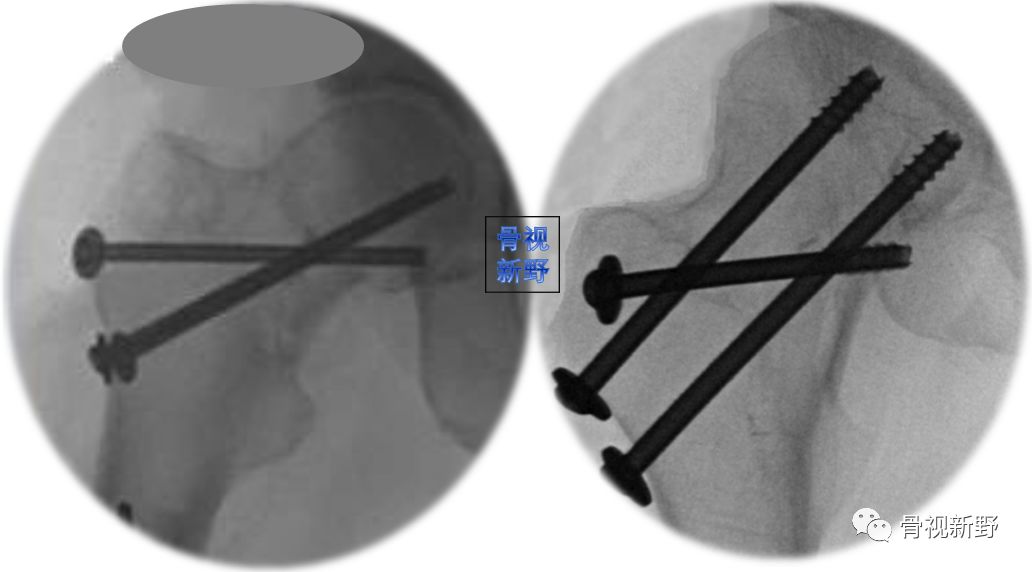

优化固定新理念——第4枚横形拉力螺钉(The 4th tranverse lag scew )

第4枚横形拉力螺钉垂直于Pauwels Ⅲ型骨折线,能对垂直的骨折面起到加压作用,可明显增加平行螺钉固定的稳定性。

在股骨颈内后侧粉碎骨折者,骨折不稳定,增加第4枚横形螺钉也可明显增加固定的稳定性。

优化固定新理念——双平面固定(又称“F”固定技术) (biplane double-supported screw fxation,BDSF技术)

螺钉分布在前后位X线片呈字母“F”形而得名。

优 点

A. 远端空心钉大角度强斜置人,增加了股骨干支撑处的力臂,保证了两支撑点间足够大的距离,从而降低两支撑点的压力负荷(如下图示):

B. 双支撑点、双平面固定具备较强的抗压和抗剪力作用,生物力学性能优越,尤其适用于骨质疏松患者(如图示):

C. 增加了螺钉间距,有效避免应力集中,降低螺钉退出、断裂等风险。

缺 点:

A. 螺钉置入有一定难度,沿股骨颈切线置入时有损伤皮质导致医源性骨折的风险。

B. 在股骨头内分散的螺钉置入有增加股骨头缺血性坏死的风险。